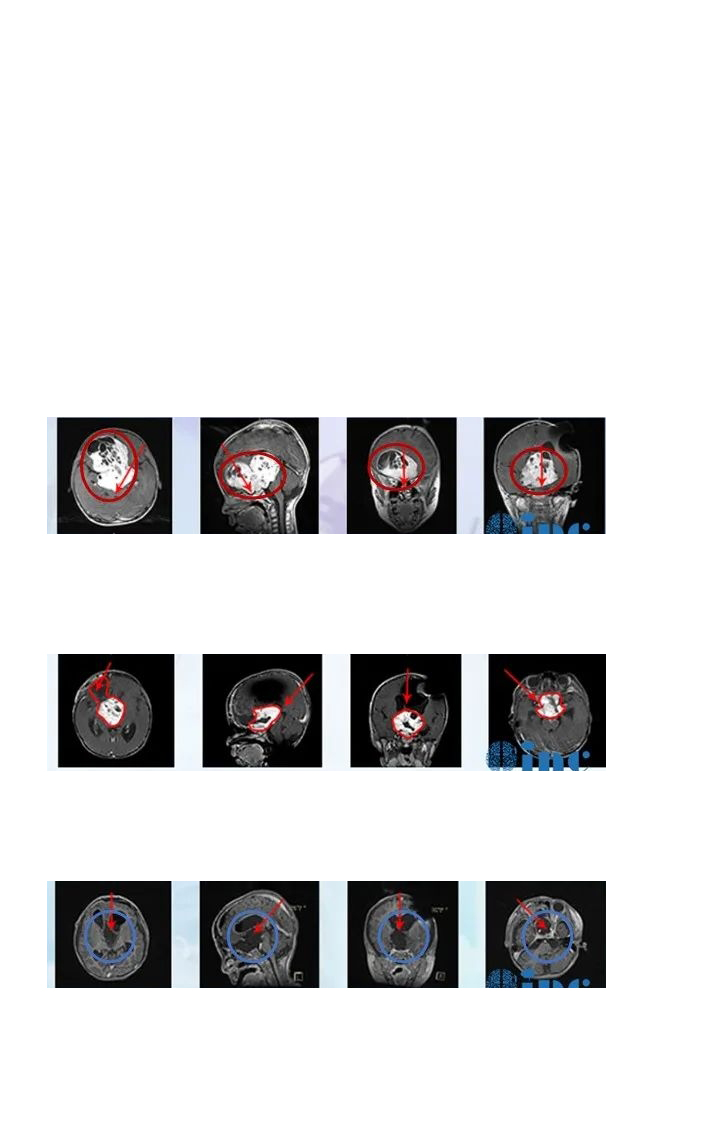

2020年末,6岁的辰辰在遭遇交通事故后,开始出现频繁头晕,就医检查发现小脑占位,提示低级别星形细胞瘤的可能,并且占位所在位置已压迫四脑室和脑干,中线结构局部左移,手术稍有不慎就可能出现瘫痪、长期昏迷等严重后果。较后,辰辰的父母选择向INC德国巴特朗菲教授寻求咨询意见,教授表示:将尽力全切脑瘤。手术风险低于1-2%,如果确诊为毛细胞型星形细胞瘤,术后复发率将低于2-3%。

2021年初,辰辰由母亲陪护赶赴德国接受教授手术治疗。在术中神经电生理检测护航下,巴教授顺利全切肿瘤,术中无神经损伤,术后辰辰恢复状态很好。回国后,辰辰的妈妈多次致谢INC,她说:"辰辰术后恢复状态很好,很多医生都看不出他做过手术,是INC和巴教授让孩子有机会继续感受这个国际的美好!"